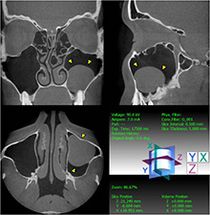

Zyste der linken Kieferhöhle (Digitale Volumentomographie, DVT)

Die Diagnostik dieser Erkrankung basiert neben der Beschwerdesymptomatik (Nasenatmungsbehinderung, Schmerzen/Druck, Sekretion, Riechminderung) auf der Endoskopie der Nase und der obligaten Schnittbilddiagnostik der Nasennebenhöhlen. Hierzu verfügen wir über die derzeit modernste Diagnostik – die Digitale Volumentomographie (DVT) –, die eine hochauflösende dreidimensionale Darstellung des Geschichtsschädels, der Nasennebenhöhlen und des Oberkiefers bei im Vergleich zur konventionellen Computertomographie deutlich niedrigerer Strahlenbelastung ermöglicht.